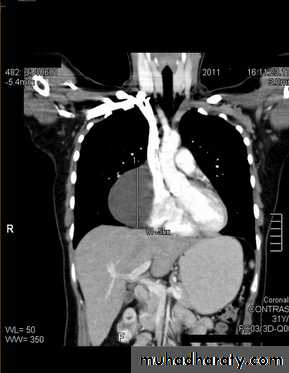

Aortic aneurysm : Dilatation of the ascending aorta may be due to aneurysm

formation or secondary to aortic regurgitation, aortic stenosis or systemic hypertension.

Substantial dilatation of the ascending aorta is needed before a bulge of the right mediastinal border can be recognized.

aortic unfolding is a commoner cause of a bulge of the right superior mediastinum than ascending aortic aneurysm.

The two common causes of aneurysm of the descending aorta are atheroma and aortic dissection.

A rarer cause is previous trauma, usually following a severe deceleration

injury.

Descending aortic aneurysms are often visible on CXRs and atheromatous aneurysms usually show calcification in their walls.

Computed tomography with intravenous contrast enhancement, magnetic resonance angiography (MRA) and/or echocardiography are very useful when aortic aneurysms are assessed .

It is important to know the extent of aortic dissections because those involving the ascending aorta are treated surgically, while those confined to the descending aorta are usually treated by an endovascular approach if conservative management is not appropriate.

Aortic dissections can be shown with CT (and MRI) and these non-invasive techniques have, in practice, replaced aortography.

Aortic aneurysm

Aortic dissection